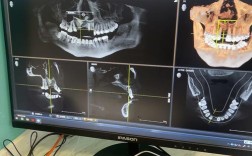

| 术后1-3个月 | 饮食:逐渐恢复正常饮食,但仍避免用术区咀嚼硬物(如坚果、骨头); 口腔卫生:可使用冲牙器(低压模式),清洁术区周边牙齿; 复查:术后1个月、3个月复查,拍摄X光片评估骨结合情况。 |

骨结合需3-6个月,期间牙齿可能轻微松动(非术区),若松动加重需警惕; 保持口腔卫生,每日刷牙2次(每次3分钟),使用牙线,预防牙周病复发; 若计划种植牙,需待医生确认骨结合良好后进行。 |

- 术后1个月:复查,评估牙龈形态、植骨材料稳定性,拍摄X光片初步观察骨缺损区域变化。

- 术后3个月:重点复查骨结合情况(植骨材料与自身骨融合程度),若为种植前植骨,医生会判断是否达到种植条件。